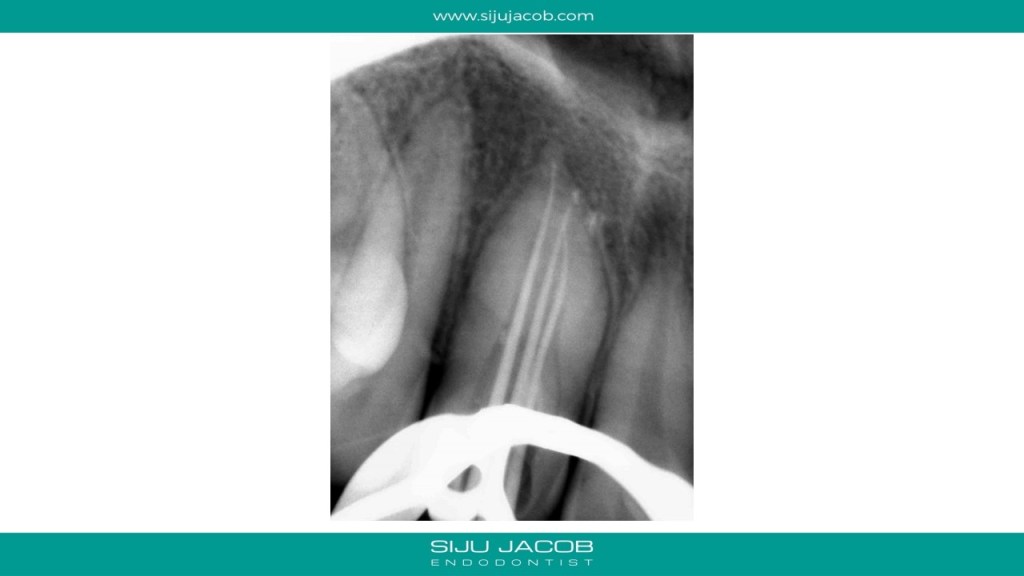

I initially thought of treating only the necrotic dens in this case because the tooth responded to heat and cold indicating that the apical lesion was probably from the dens. But, after the initial visits, the patient had persistent pain. So, I opened up both the canals, one of which was very hyperemic. I put this tooth on calcium hydroxide for 12 months and Obturated after the lesion healed. Placed Fiber-posts to strengthen the tooth. No crown for now.

Do you think your Apical enlargement is sufficient, though lesion has healed

Yes, why enlarge more?